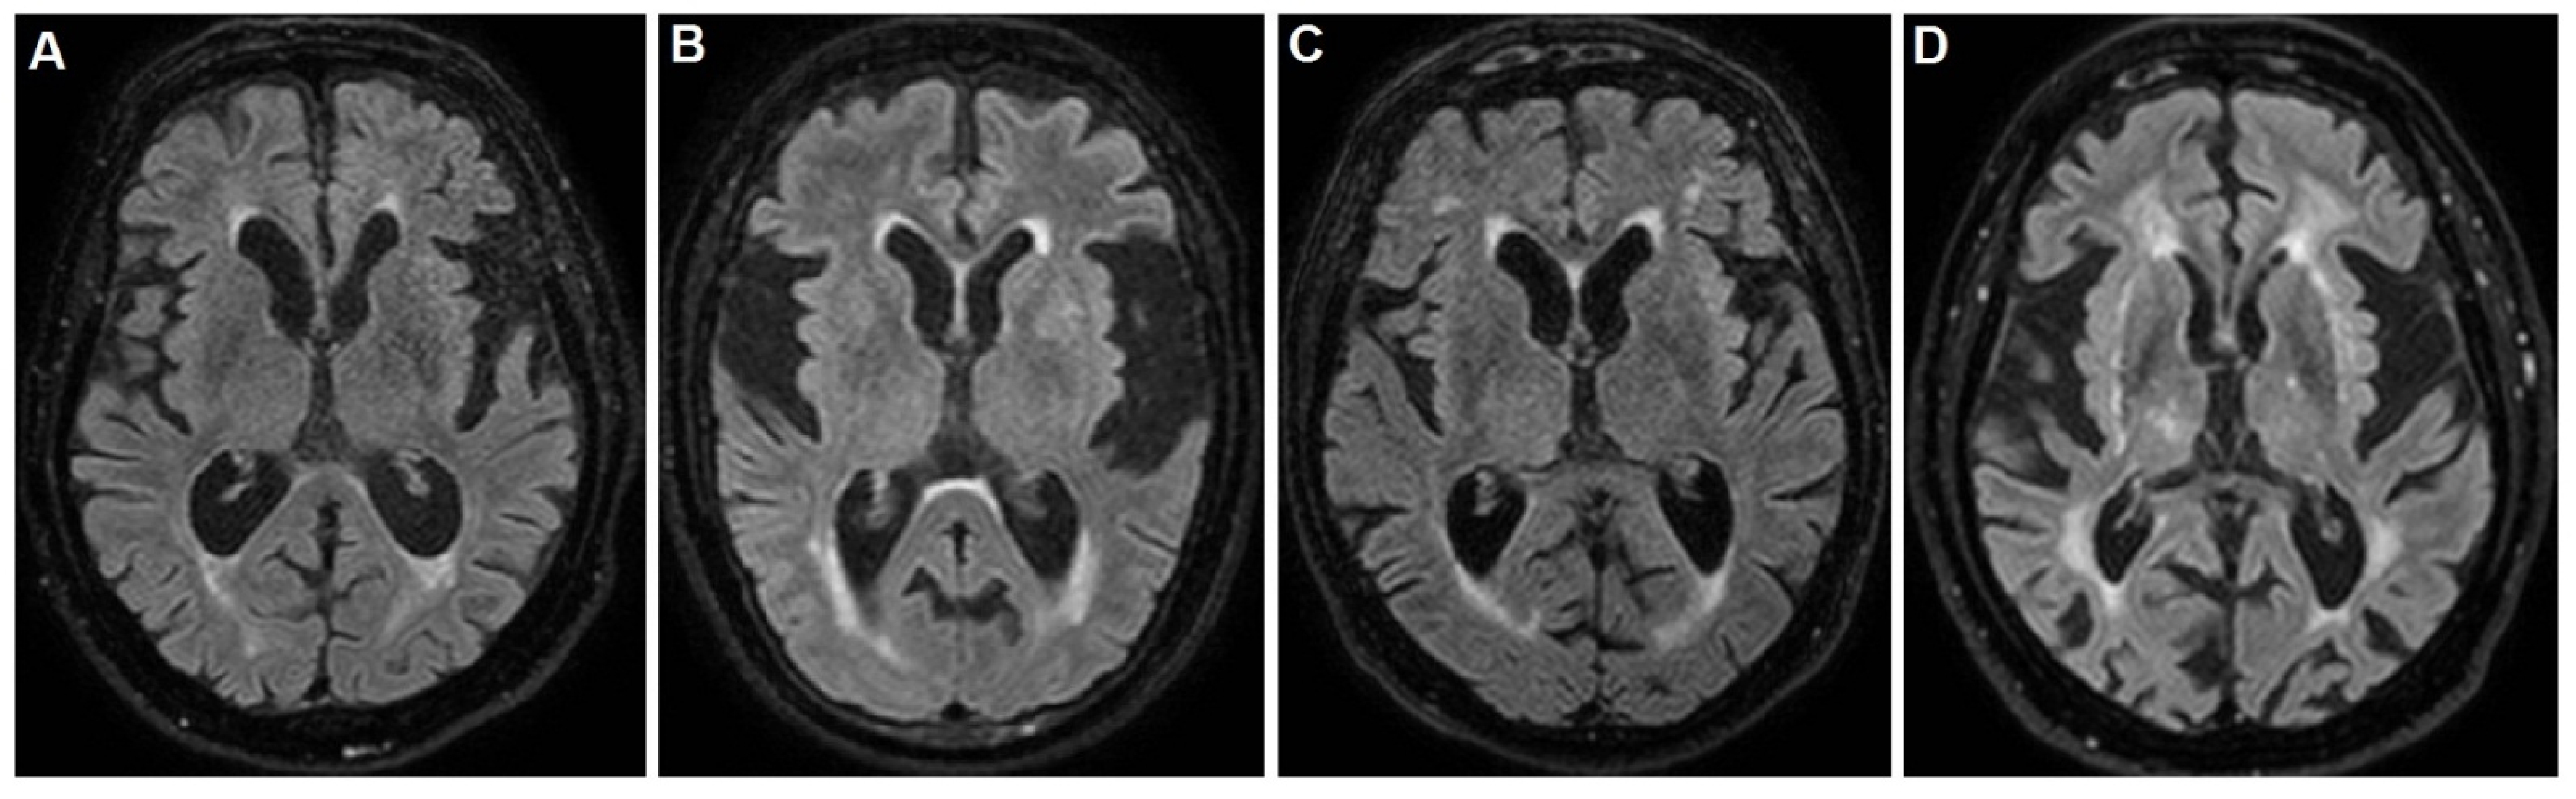

The neuropsychological tests, including the Mini Mental State Examination (MMSE) [13], were not applicable and the Barthel index was 25/100. Brain magnetic resonance imaging (MRI) evidenced the insular atrophy, with greater left expression, the enlargement of the ventricular system and subarachnoid spaces with mild hyperintensity of the periventricular white matter, as shown in Figure 1A.

The MMSE, as well as other neuropsychological tests, were not applicable and the Barthel index was 25/100. Brain MRI evidenced the insular atrophy, with greater left expression, the enlargement of subarachnoid spaces with diffuse deepening of the cortical sulci and a thinning of the cortical mantle, especially at the fronto-temporal lobes, as shown in Figure 1B. After several weeks from the singing onset, the patient underwent a Trazodone and Benzodiazepine based therapy, without any improvement. Finally, she underwent the Haloperidol 2% solution, at a dosage of 0.5 mg three times daily, with a dramatic improvement.

During this worsening phase, the MMSE, as well as other neuropsychological tests, were not applicable. The Barthel index score was 20/100. Brain MRI evidenced a slight diffuse shrinkage of the subcortical grey matter with several hyperintense lesions at semioval centers and the insular atrophy, with greater left expression, as shown in Figure 1C. Ten days after the singing onset, the patient underwent hospitalization due to the dyspnea and respiratory insufficiency. In this case, the patient already was taking 10 mg daily of Memantine, 75 mg daily of Quetiapina in refracted dose manner and 1 mg three times daily of Haloperidol, due to his deliriant state. However, the therapeutic response of the singing was poor, and the patient developed a respiratory insufficiency with hospitalization and loss to follow-up. The consultant neurologist was R.D.M.

The MMSE, as well as other neuropsychological tests, were not applicable. The Barthel index score were 10/100. Brain MRI evidenced a subcortical chronic ischemia and vascular encephalopathy with periventricular diffuse hyperintensity, as well as the atrophy of insula, as shown in Figure 1D. The neurological examination found difficult access to the patient, due to the singing and a severe deterioration in all superior cortical functions, resulting in aphasia, agnosia and apraxia, configuring the so-called alogic syndrome. In addition, slight spastic rigidity in all limbs and poor environmental contact were noted. After infusional rehydration, the 5 mg daily Haloperidol therapy greatly reduced the singing. However, the other cognitive disturbances persisted with apathy and poverty of speech and its contents. Finally, the patient was sent to a territorial rehabilitation treatment and assistance path with a prescription of 10 mg daily of Memantine.

Figure 1. Brain magnetic resonance imaging (MRI) short tau inversion recovery (STIR) sequences of (A) patient 1: note the enlargement of the ventricular system and subarachnoid spaces with mild hyperintensity of the occipital horns periventricular white matter; (B) patient 2: note the enlargement of subarachnoid spaces with diffuse deepening of the cortical sulci and a thinning of the cortical mantle, especially at the fronto-temporal lobes. The hyperintensity of the occipital horns periventricular white matter is also visible; (C) patient 3: note the slight diffuse shrinkage of the subcortical grey matter with several hyperintense lesions at semioval centers; (D) patient 4: note the subcortical chronic ischemic lesions with vascular encephalopathy and periventricular diffuse hyperintensity. Note the atrophy of insula as a common feature of these brains.